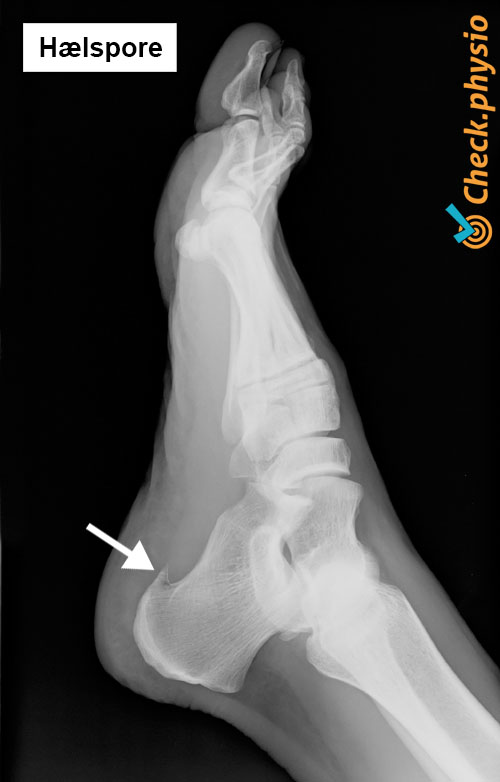

Hælspore

En hælspore er en torneliknende forkalkning der leddbåndsom fester til hælbenet. Forskning viser at de fleste eldre har en hælspore. Dette gir imidlertid ikke alltid symptomer. En hælspore utvikles sannsynligvis ved langvarig trykk på et lite område av hælbenet. Det er en gradvis prosess som har større sjanse for å utvikle seg med alderen.

Overdreven bentilvekst ved en hælspore kan irritere nærliggende strukturer. Noen leger mener at en hælspore i enkelte tilfeller også er en funksjonell tilpasning fra kroppen for å beskytte hælbenet mot overbelastning.